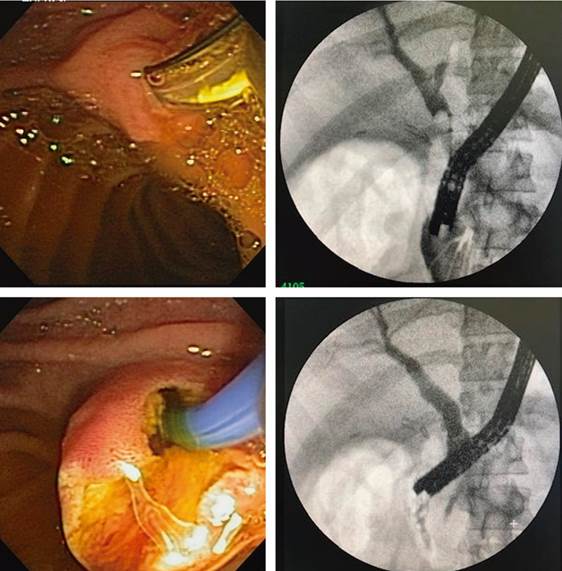

The second stage was performed ten days later under sedation and after gastroscopy to verify adequate passage to the duodenum. The side-viewing duodenoscope was advanced through the apposing stent to the duodenal papilla, and the usual ERCP was performed with a sufficient papillotomy and stone extraction. There was no bleeding or complication during the procedure (Figure 5). Upon removal of the duodenoscope, the position of the apposing stent was verified, and emptying of the gastric chamber was performed by aspiration.

The stent was left in position for two more weeks; it was removed endoscopically without difficulty, and the jejunogastric fistula was confirmed to be contracting.